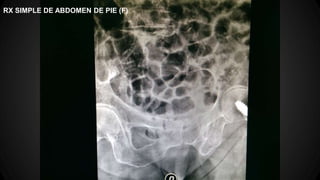

●RX SIMPLE DE ABDOMEN PIE: Gran distensión del I. delgado y intestino grueso.

RX SIMPLE DE ABDOMEN DE PIE (F)

Rx de abdomen simple de pie